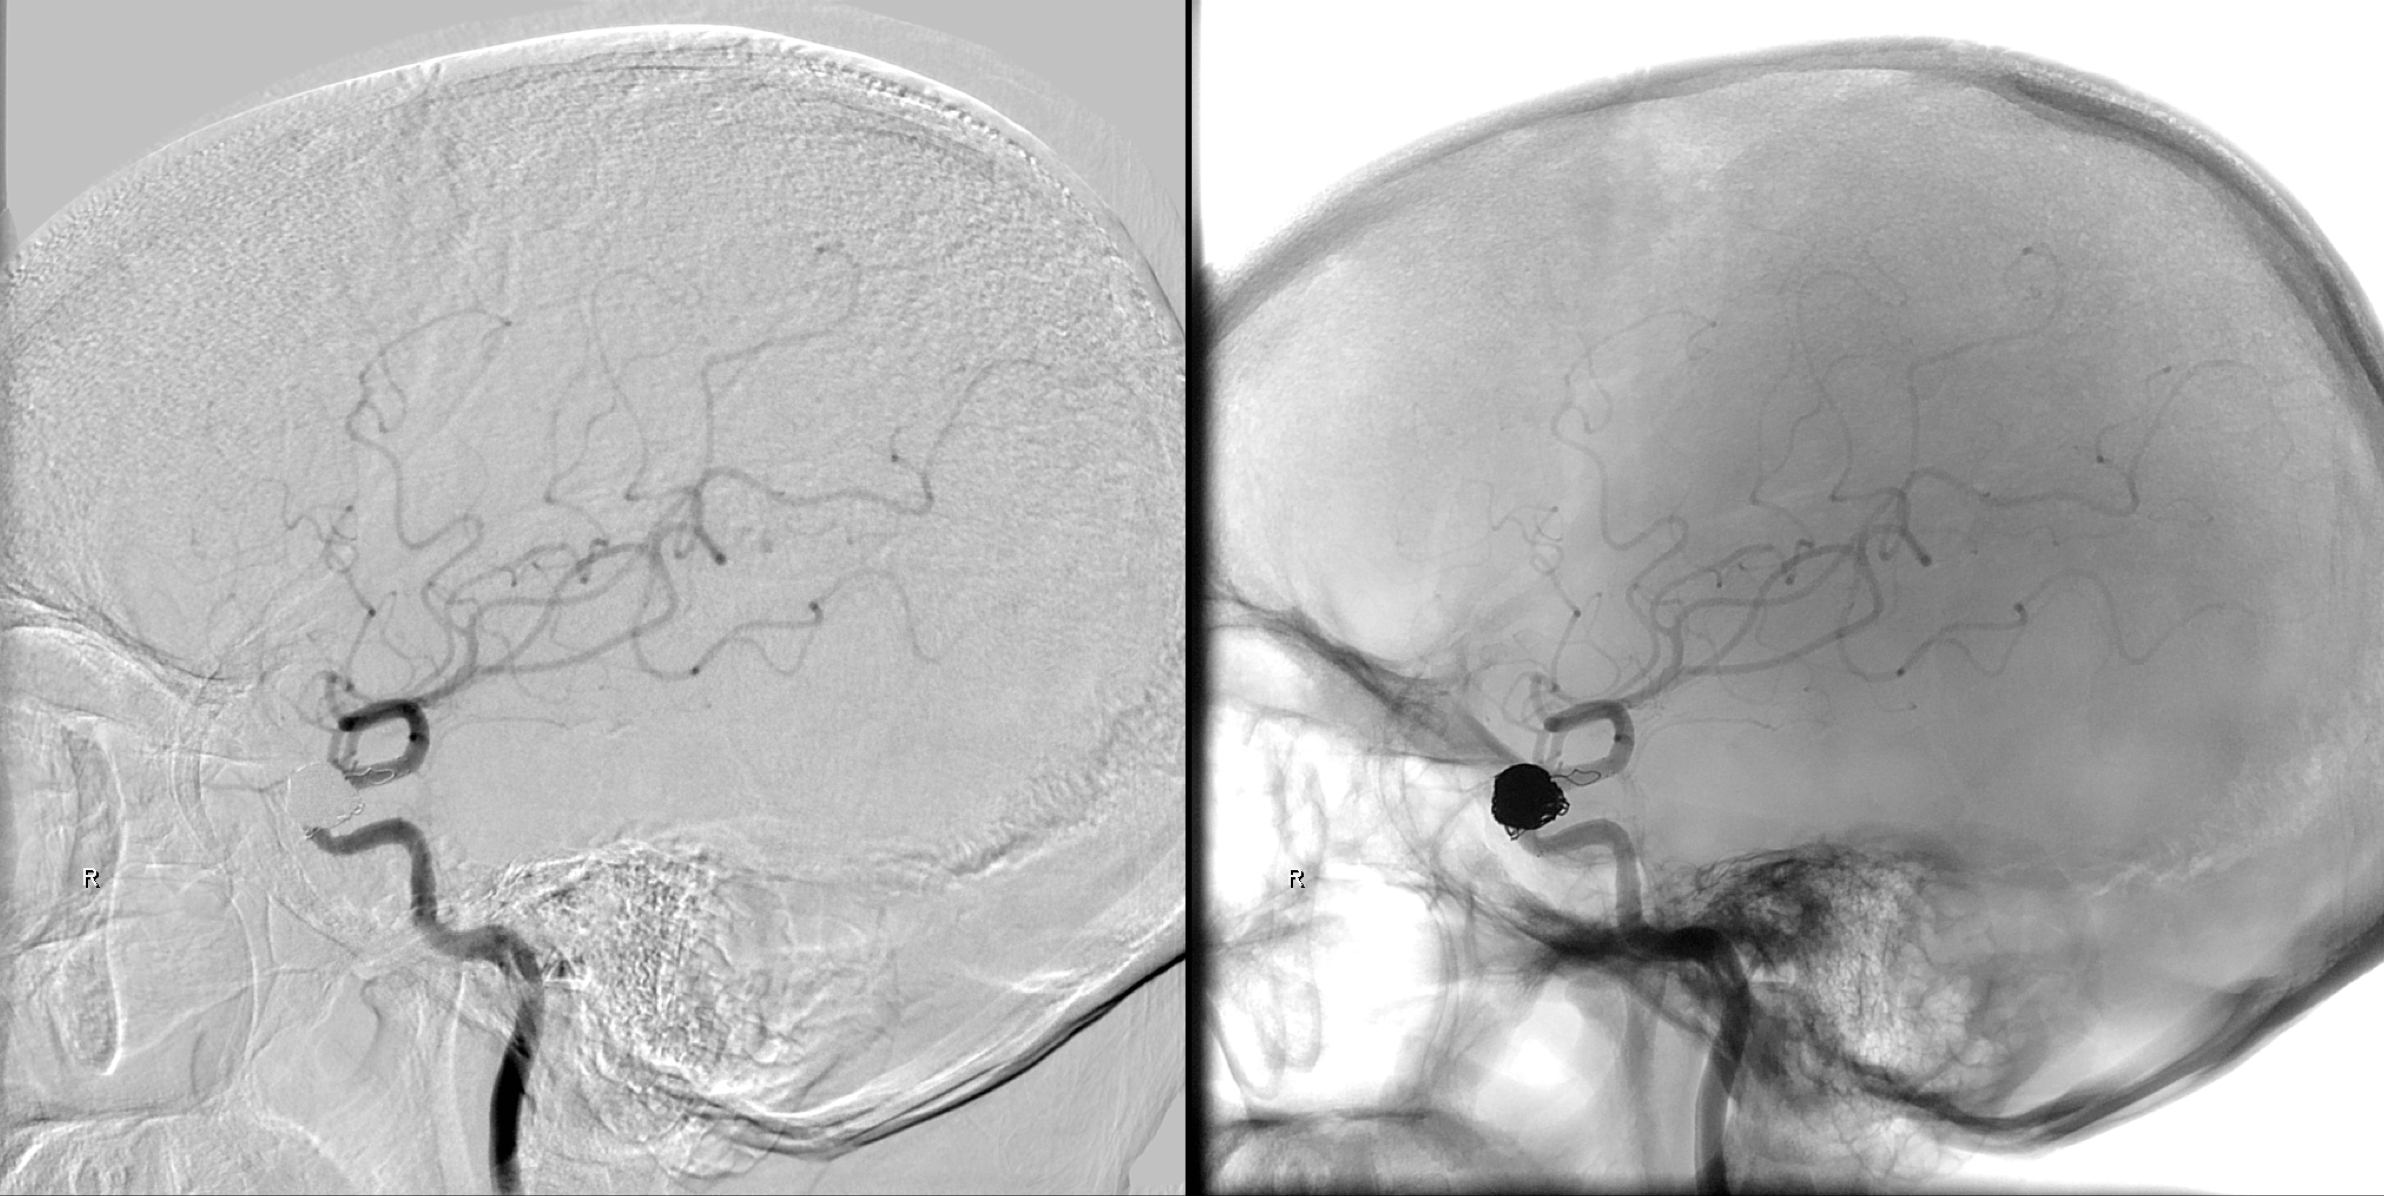

术后1年于2017年3月10日再次入院复查。右侧颈内动脉正位造影及蒙片显示:动脉瘤未见复发!

右侧颈内动脉侧位造影及蒙片显示:动脉瘤未见复发!

正侧位蒙片显示:支架及弹簧圈形态良好!

右侧颈内动脉三维重建:动脉瘤未见复发,载瘤动脉通畅!

右侧颈内动脉三维重建:动脉瘤未见复发,载瘤动脉通畅!